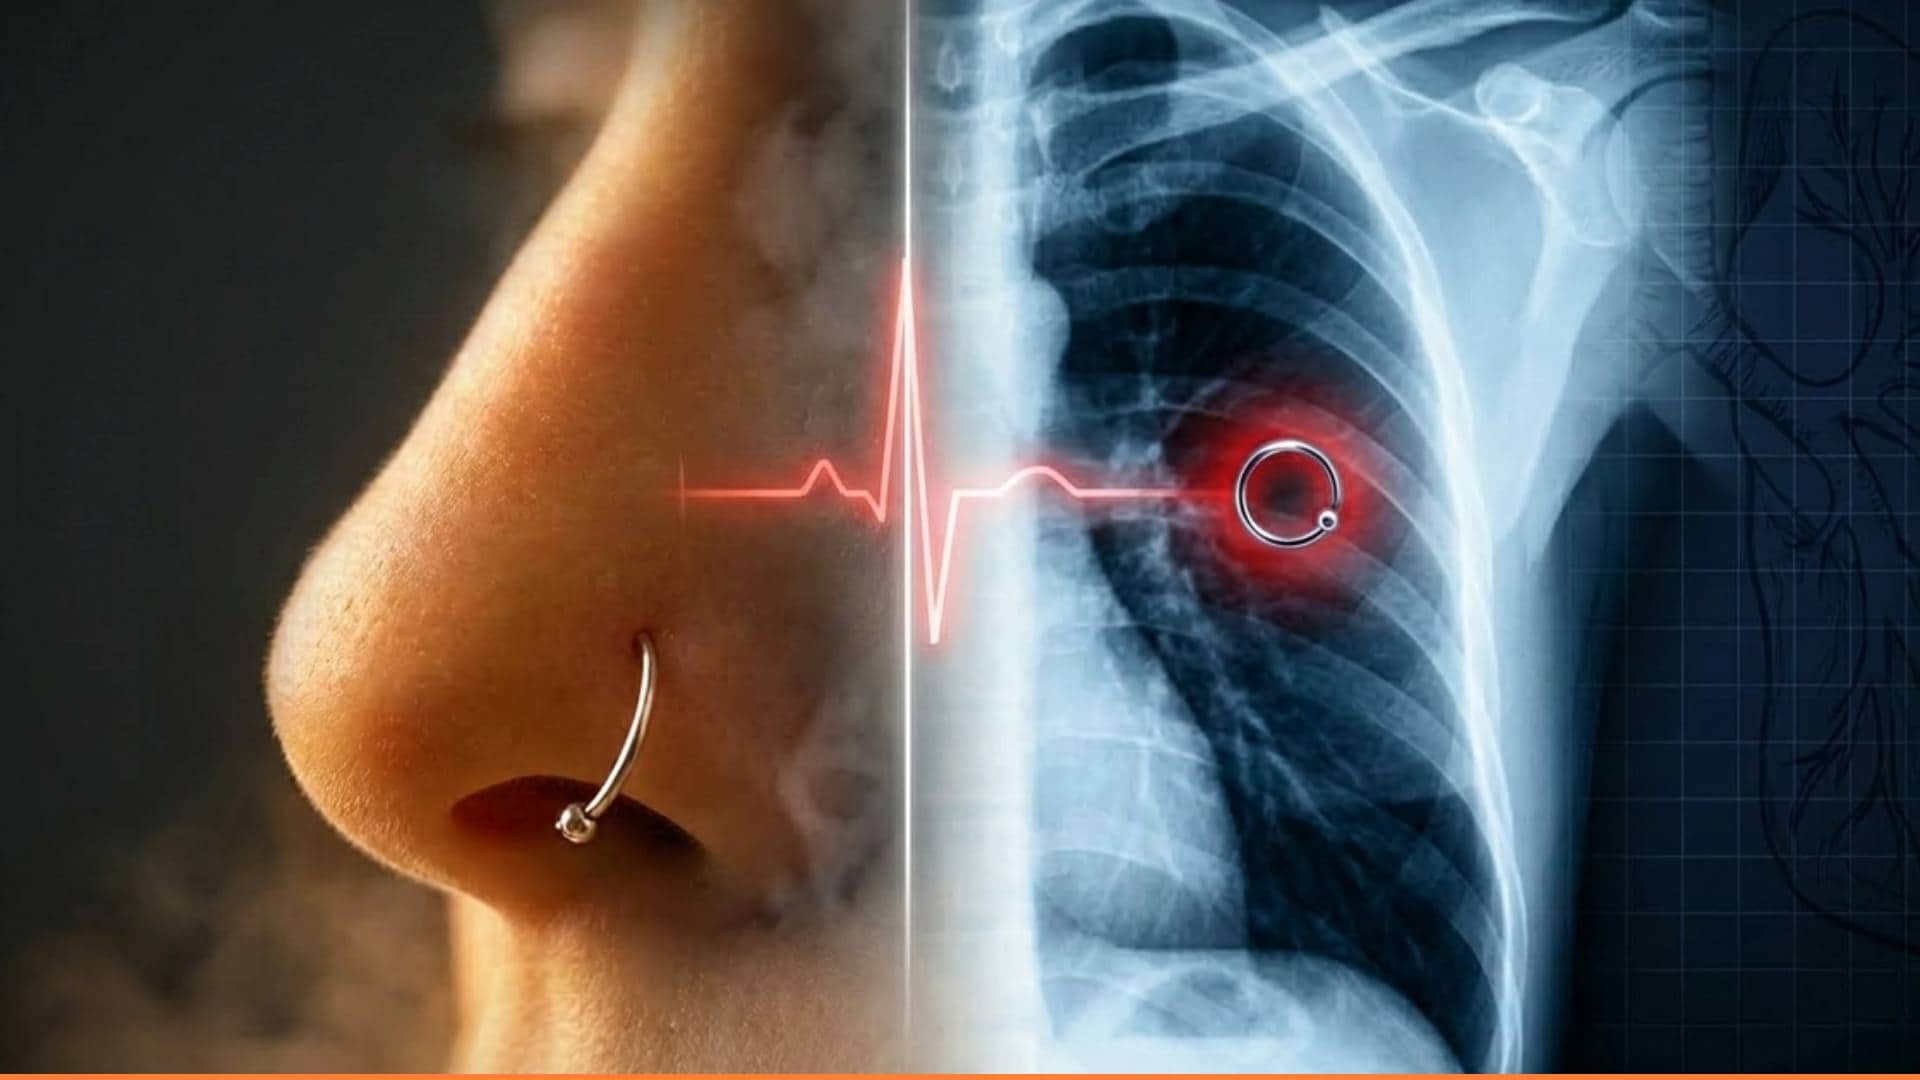

Weird News: मेक्सिको की 26 वर्षीय मोनिका डेयानिरा की नाक में पहनी छोटी सी रिंग नींद के दौरान अनजाने में निकलकर सांस के रास्ते उनके फेफड़ों तक पहुंच गई। इसके बाद जांच के दौरान जब एक्स-रे किया गया तो डॉक्टर भी चौंक गए।

जांच के दौरान जब एक्स-रे किया गया, तो डॉक्टर भी चौंक गए। रिपोर्ट में साफ दिखा कि उनके फेफड़ों के अंदर गहराई में नाक की रिंग फंसी हुई है। सबसे हैरान करने वाली बात यह थी कि मोनिका को काफी समय तक यह एहसास भी नहीं हुआ कि उनकी नाक की रिंग गायब हो चुकी है।

मोनिका के मुताबिक, संभवतः वह पीठ के बल सो रही थीं, तभी रिंग का स्क्रू ढीला होकर निकल गया और गहरी सांस लेते समय वह सीधे गले से होते हुए फेफड़ों में चली गई। यह छोटी सी धातु की चीज बेहद खतरनाक साबित हो सकती थी, क्योंकि वह दिल की मुख्य धमनी एओर्टा से महज आधा मिलीमीटर दूर थी। अगर रिंग जरा भी खिसकती, तो जान जाना तय था।